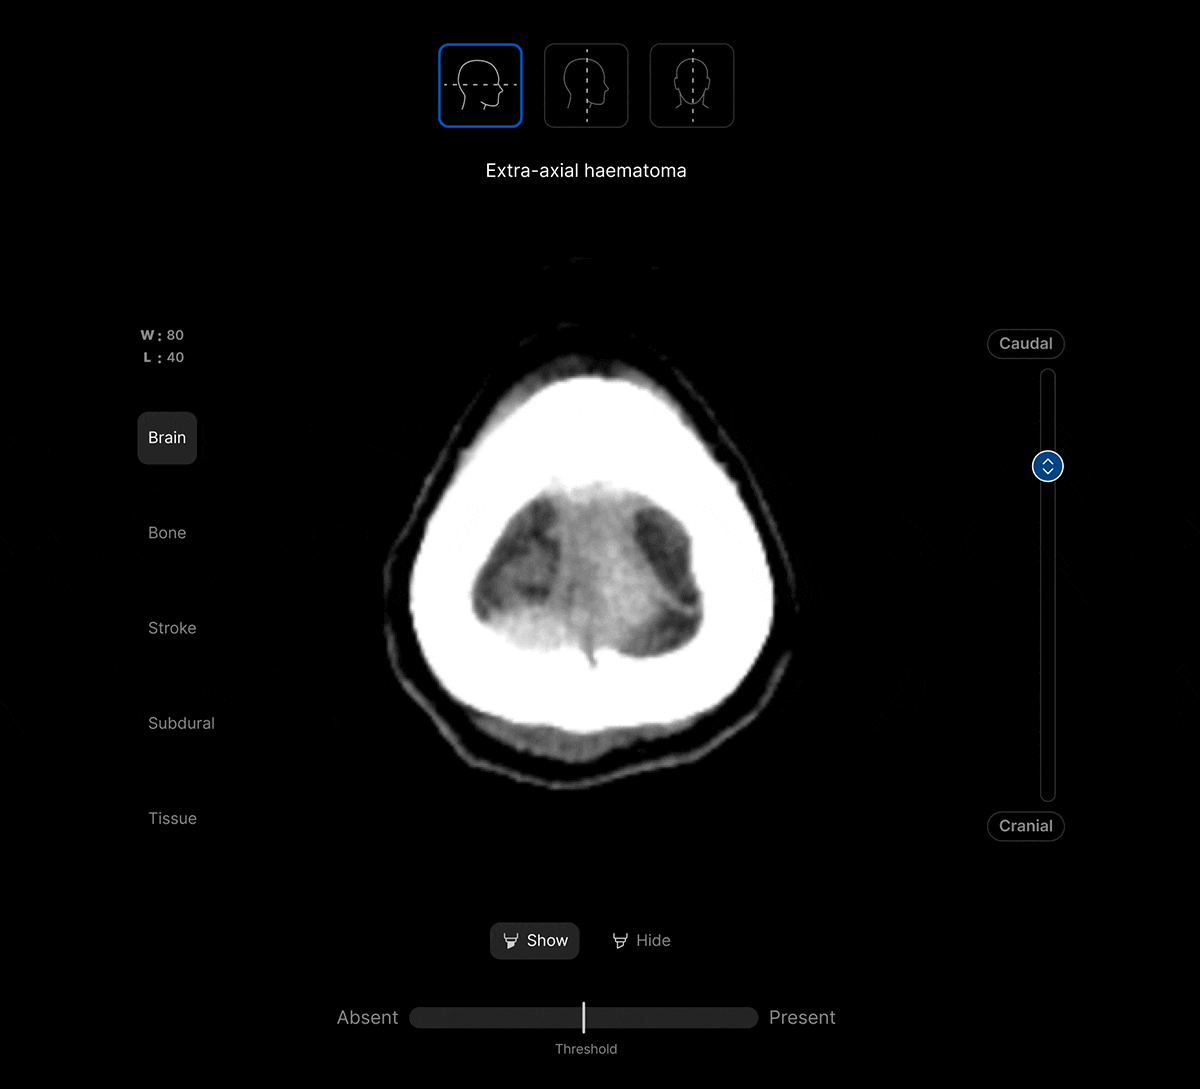

View findings within preset subdural, bone, brain, soft tissue and stroke views to provide additional context to the AI results.

AI analysis viewable on different head CT slices.

View the findings in sagittal, axial and coronal projections.